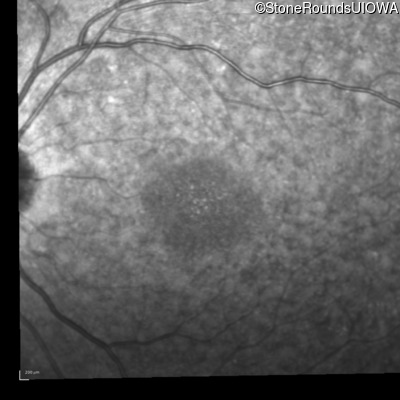

| AR Stargardt Disease | ABCA4 | IVS21-2 A>G | Pro1380Leu CCG>CTG | AR |